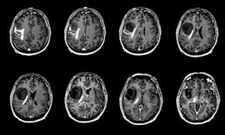

Malign tümörler, kanserli hücrelerin kontrolsüz bir şekilde bölünmesi ve çoğalması sonucu oluşan, çevre dokulara zarar verebilen ve metastaz yapma potansiyeline sahip olan tümörlerdir. Bu tümörler, vücutta çeşitli sistemleri etkileyebilir ve ciddi sağlık sorunlarına yol açabilir. Bu makalede, malign tümörlerin belirtileri, tanı yöntemleri ve tedavi seçenekleri ele alınacaktır. Malign Tümörlerin BelirtileriMalign tümörlerin belirtileri, tümörün türüne, büyüklüğüne ve bulunduğu bölgeye göre değişiklik gösterebilir. Ancak, genel olarak aşağıdaki belirtiler sıkça gözlemlenmektedir:

Bu belirtiler malign tümörlerin varlığını gösterebileceği gibi, başka sağlık sorunlarının belirtisi de olabilir. Bu nedenle, belirtilerin ortaya çıkması durumunda bir sağlık uzmanına başvurulması önemlidir. Malign Tümörlerin Tanı YöntemleriMalign tümörlerin tanısı, çeşitli yöntemler kullanılarak konulmaktadır. Bu yöntemler arasında:

Bu tanı yöntemleri, malign tümörlerin varlığını belirlemek ve tümörün türünü, evresini değerlendirmek amacıyla kullanılmaktadır. Erken tanı, tedavi sürecinde büyük bir öneme sahiptir. Malign Tümörlerin Tedavi SeçenekleriMalign tümörlerin tedavisi, tümörün türüne, evresine ve hastanın genel sağlık durumuna bağlı olarak değişiklik göstermektedir. Başlıca tedavi yöntemleri şunlardır: